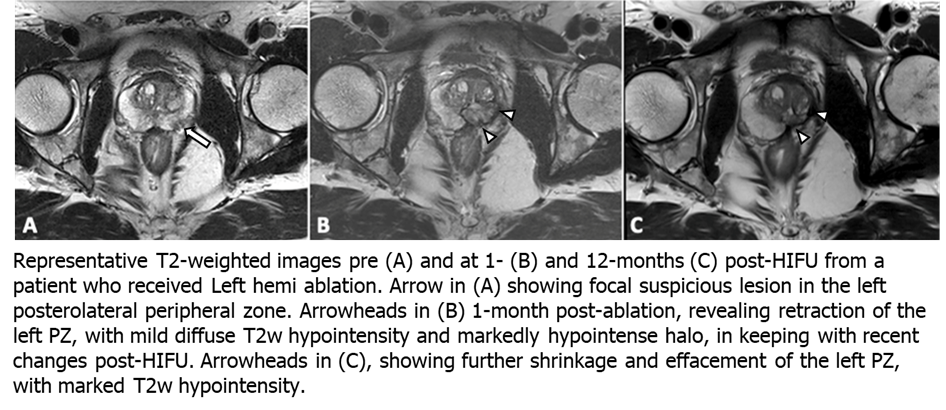

A total of 57 mpMRIs were included in this analysis. Preoperative median prostate size was 40.6 cc [23.6 - 52.1 cc]. One month after HIFU, prostatic volumetric change was variable with a median increase of 3% [-13% - 22%] (p = 0.51). At twelve months there was a -17% [-23% - -8%] reduction in prostate volume compared to baseline (p = 0.001). Prostate rotation was seen in 12/19 men with a median angulation of 5 ̊ degrees and max angulation of 20 ̊ at one and 12 months with 83% of rotations in the direction of hemi-ablation. Figure 1 shows representative pre-operative (A), one-month (B) and 12-month (C) T2-weighted MRI changes seen after left hemi-gland HIFU ablation. A summary of pre- and post-operative statistics including follow-up biopsy are shown in Table 1.

Anatomical mpMRI changes following HIFU therapy